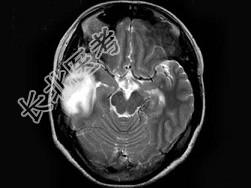

- 单项选择题女,25岁, 头痛3个月,头颅MRI平扫及增强扫描如图, 最可能的诊断是 ( )